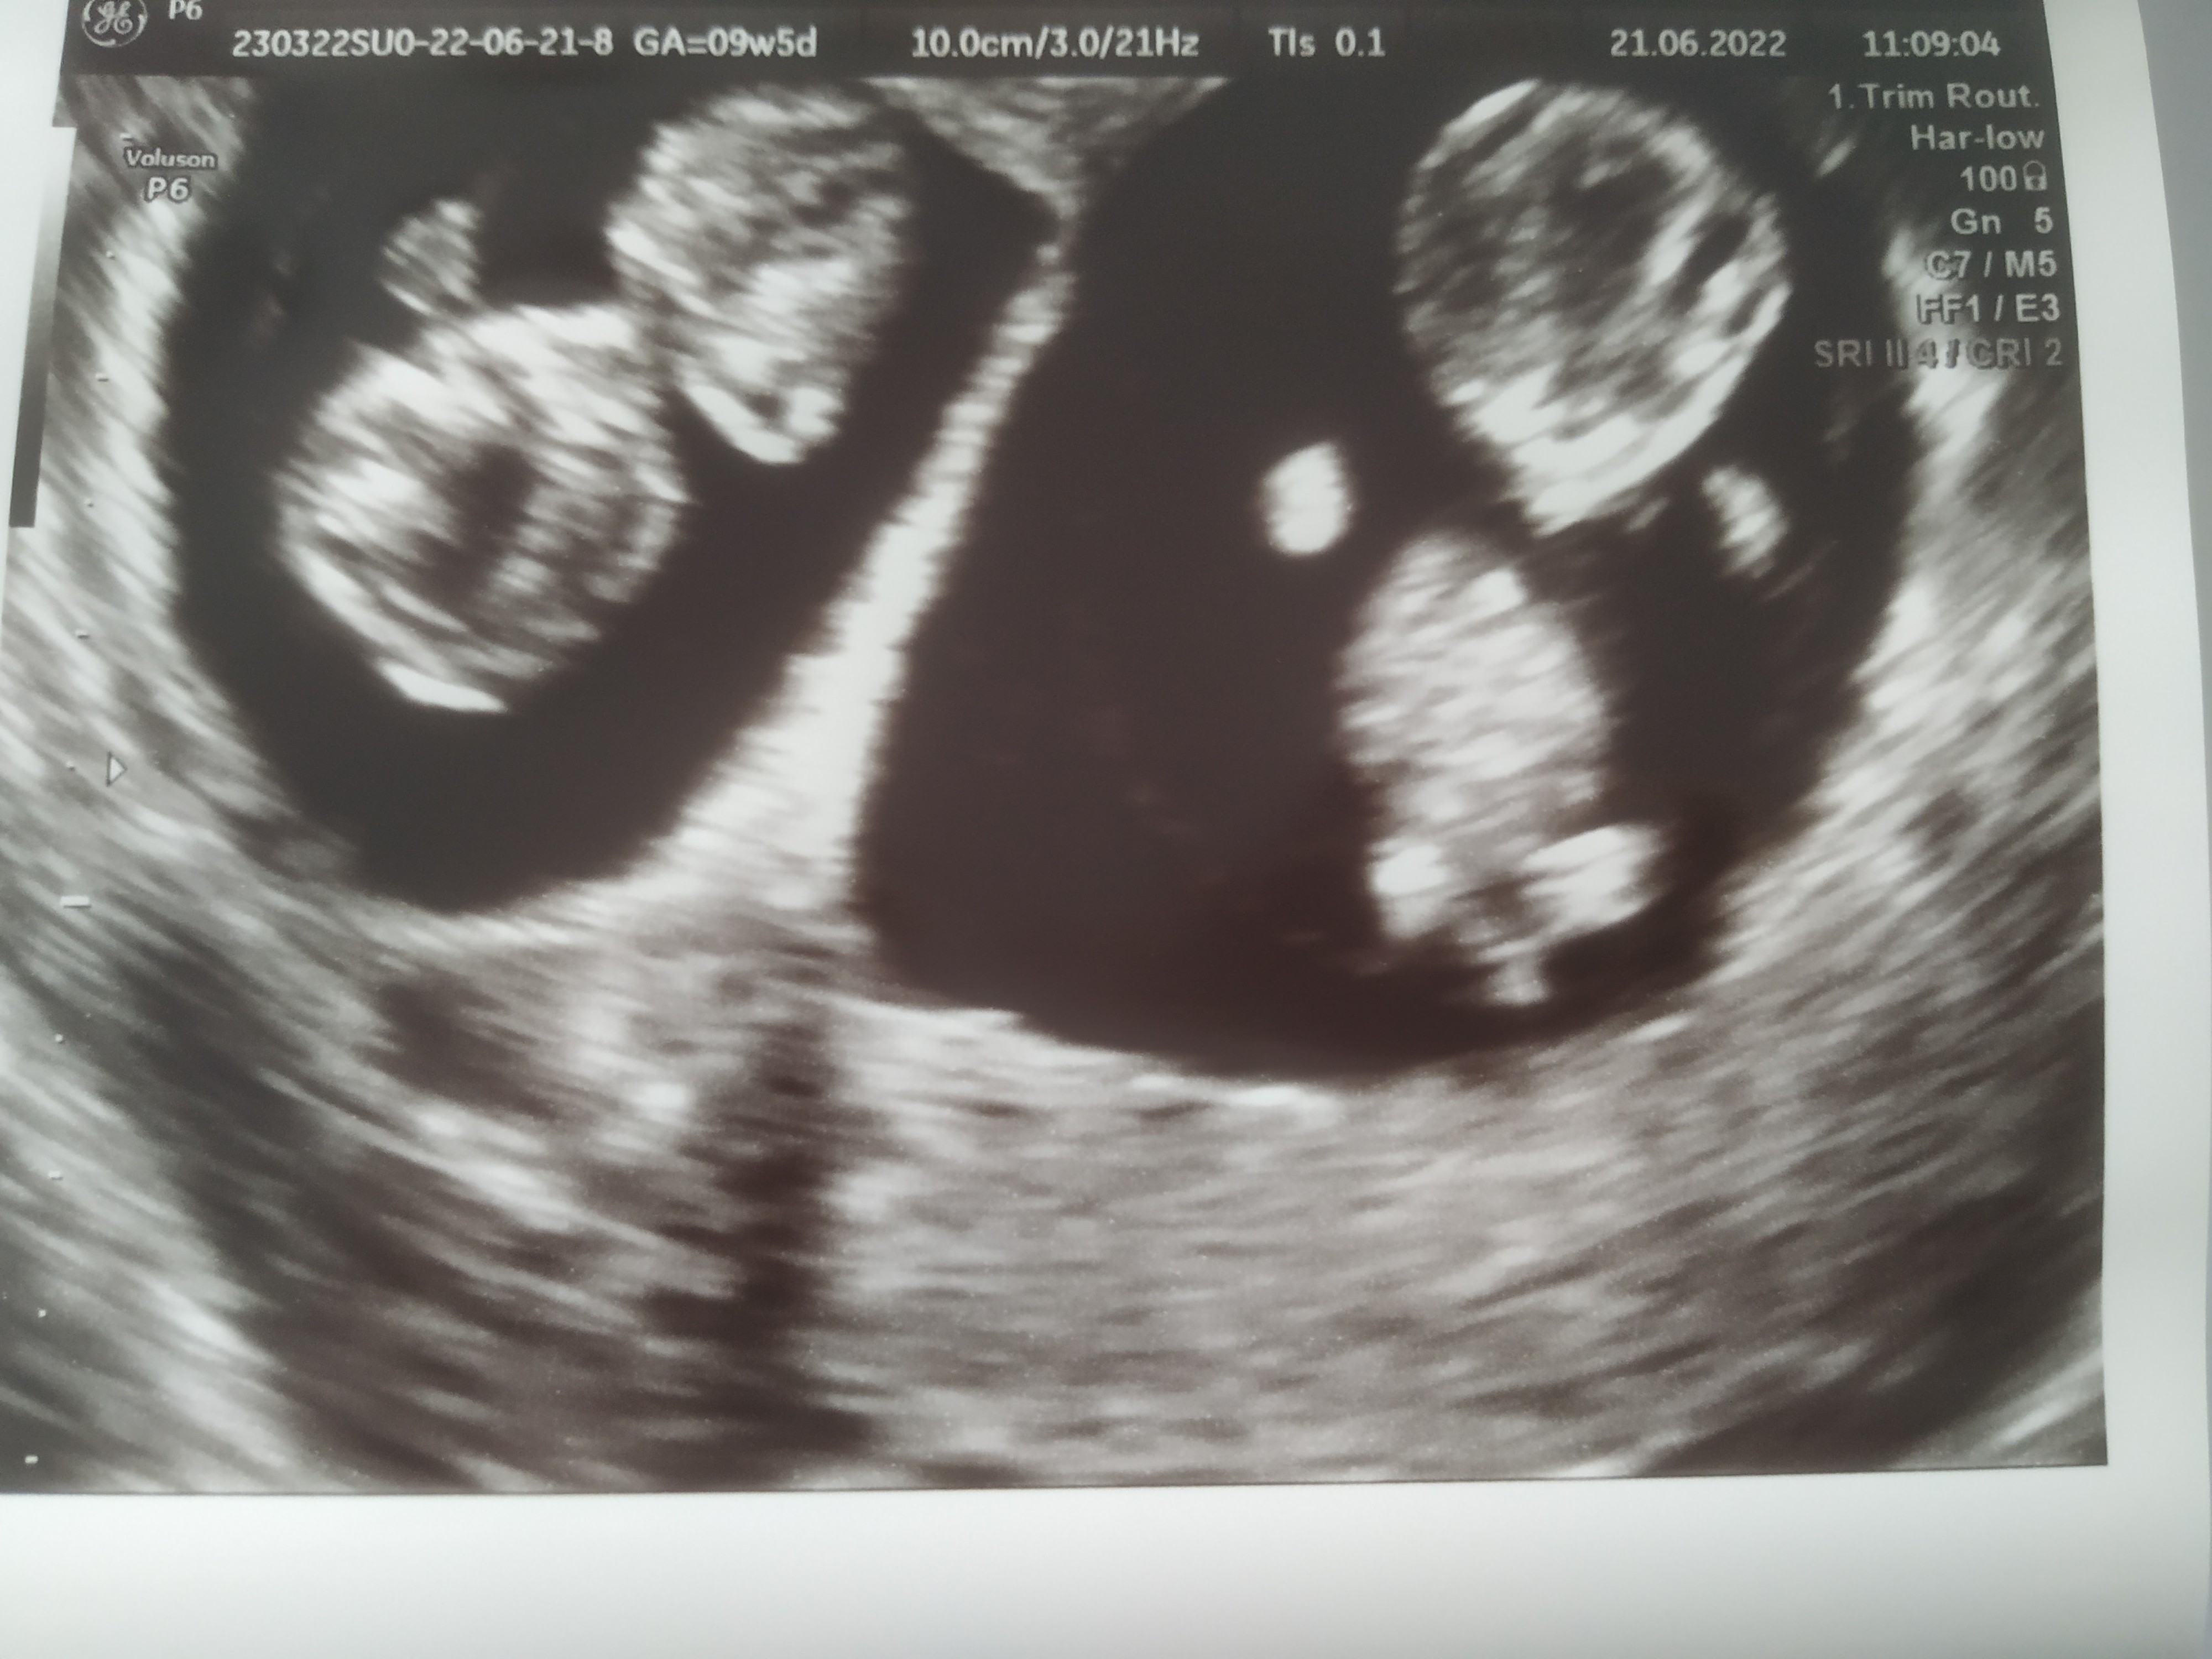

Ale super! jakie MiśkiJuż po, narazie wszytako ok10 tydzien, tak jak z miesiączki, dzieciaki już machaly rękami i nóżkami i słyszałam serduszka

szok, fotka na dole

Pięknie wyglądająJuż po, narazie wszytako ok10 tydzien, tak jak z miesiączki, dzieciaki już machaly rękami i nóżkami i słyszałam serduszka